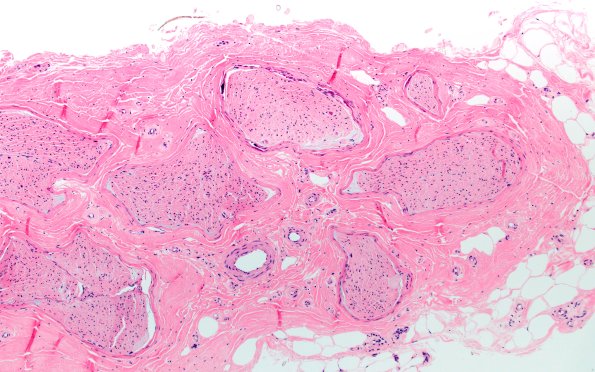

Washington University Experience | PERIPHERAL NEUROPATHY | 9B PERINEURITIS & PERINEURIAL PATHOLOGY | 6A1 (Case 6) H&E 10X

Case 6 History ---- The patient is a 68-year-old woman with a history of neuropathy, diabetes, venous stasis, Open Reduction and Internal Fixation (ORIF) of right distal tibia and fibula, and necrobiosis diabeticorum of the left lower extremity. Operative procedure: Biopsy of right gastrocnemius and right sural nerve. ---- 6A1-4 There are frequent prominent perineurial calcifications but no evidence of vasculitis or inflammation.